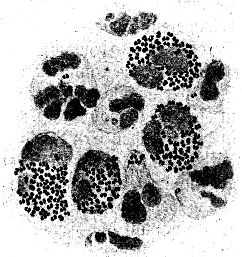

Abb. 2

Abb. 2.

Ausstrichpräparat von menschlichem Zahnschleim, gefärbt, etwa 1000fach vergrößert. Mannigfaltige Bakterien in buntem Gemisch.